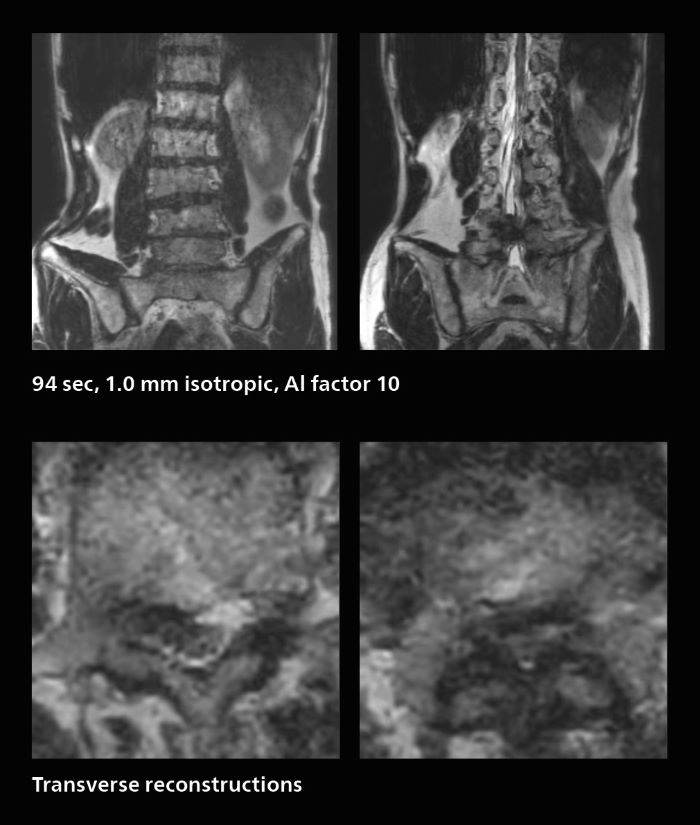

Fast lumbar spine imaging for successful exam of patient in pain

A patient arrived saying that undergoing MRI was not possible because of severe back pain and leg pain, was imaged with SmartSpeed in only 94 seconds. The scan was diagnostic and afterwards the patient confirmed that it only took a little while. Performed on Elition X.

Fast lumbar spine MRI with SmartSpeed of a patient in pain produced a successful isotropic diagnostic scan in only 94 minutes.

The hospital’s fast lumbar spine ExamCard includes T2W SpineVIEW, 1:40 min, 1.0 mm isotropic, acceleration factor 12.